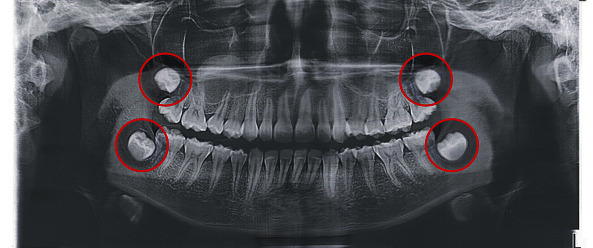

사랑니 발치 후 붓는 이유

사랑니는 일반 치아보다 큰 경우가 많습니다.

게다가 잇몸 깊숙한 곳에 있어요.

큰 치아가 깊숙한 곳에 단단히 박혀있으니,

이런 치아를 뽑아내려면

주변 조직에 자극이 가해질 수밖에 없죠.

부종이 심할 수밖에 없는

매복 사랑니 발치의 경우에서 자주 나타나요.